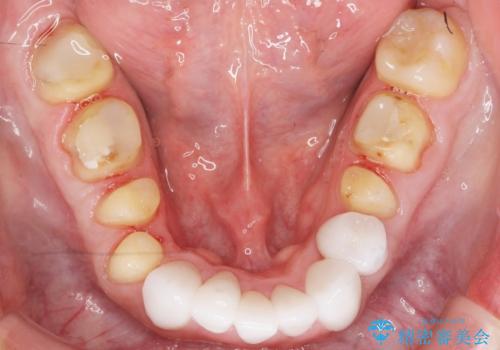

矯正治療とホワイトニングを提案しましたが希望されず、「接客関係の仕事で矯正治療は考えられない、短期間で治療を終わらせたい、ホワイトニングでは難しい位の人工的な白さにしたい」とのご要望により、治療前にワックスアップ模型を作製し何度もコンサルテーションを重ね、治療方針を決定しました。

歯頚ラインが変えられないことや天然歯を削るリスクをご理解頂いた上で、オールセラミッククラウンによる補綴治療を行いました。(見えない奥歯のみ天然歯のままとしました)

下の前歯1本だけ歯軸を変えるために神経をとり根管治療を行っております。

それ以外の歯は神経をとらずに済むよう、慎重かつ丁寧に歯の形態を整えました。

- ¥2,790,000 (仮歯×24本、根管治療×1本、土台×1本、クラウン×24本、セラミックインレー×1)費用は治療当時の料金となります

クラウンの色味・形態の修正や患者様のお仕事のご都合で来院できない期間があったことにより、予想より治療期間が長くなってしまいましたが、審美的な仕上がりにご満足頂けました。

クラウンの色味に関して、自然な白さ(シェードA1~NW0.5)のクラウンを作製・試適したところ「もっと白くしたい」と希望され、当院で最も明度の高い色(シェードNW0)に修正しました。

被せ物の種類:オールセラミッククラウン スタンダード (シェード:NW0)